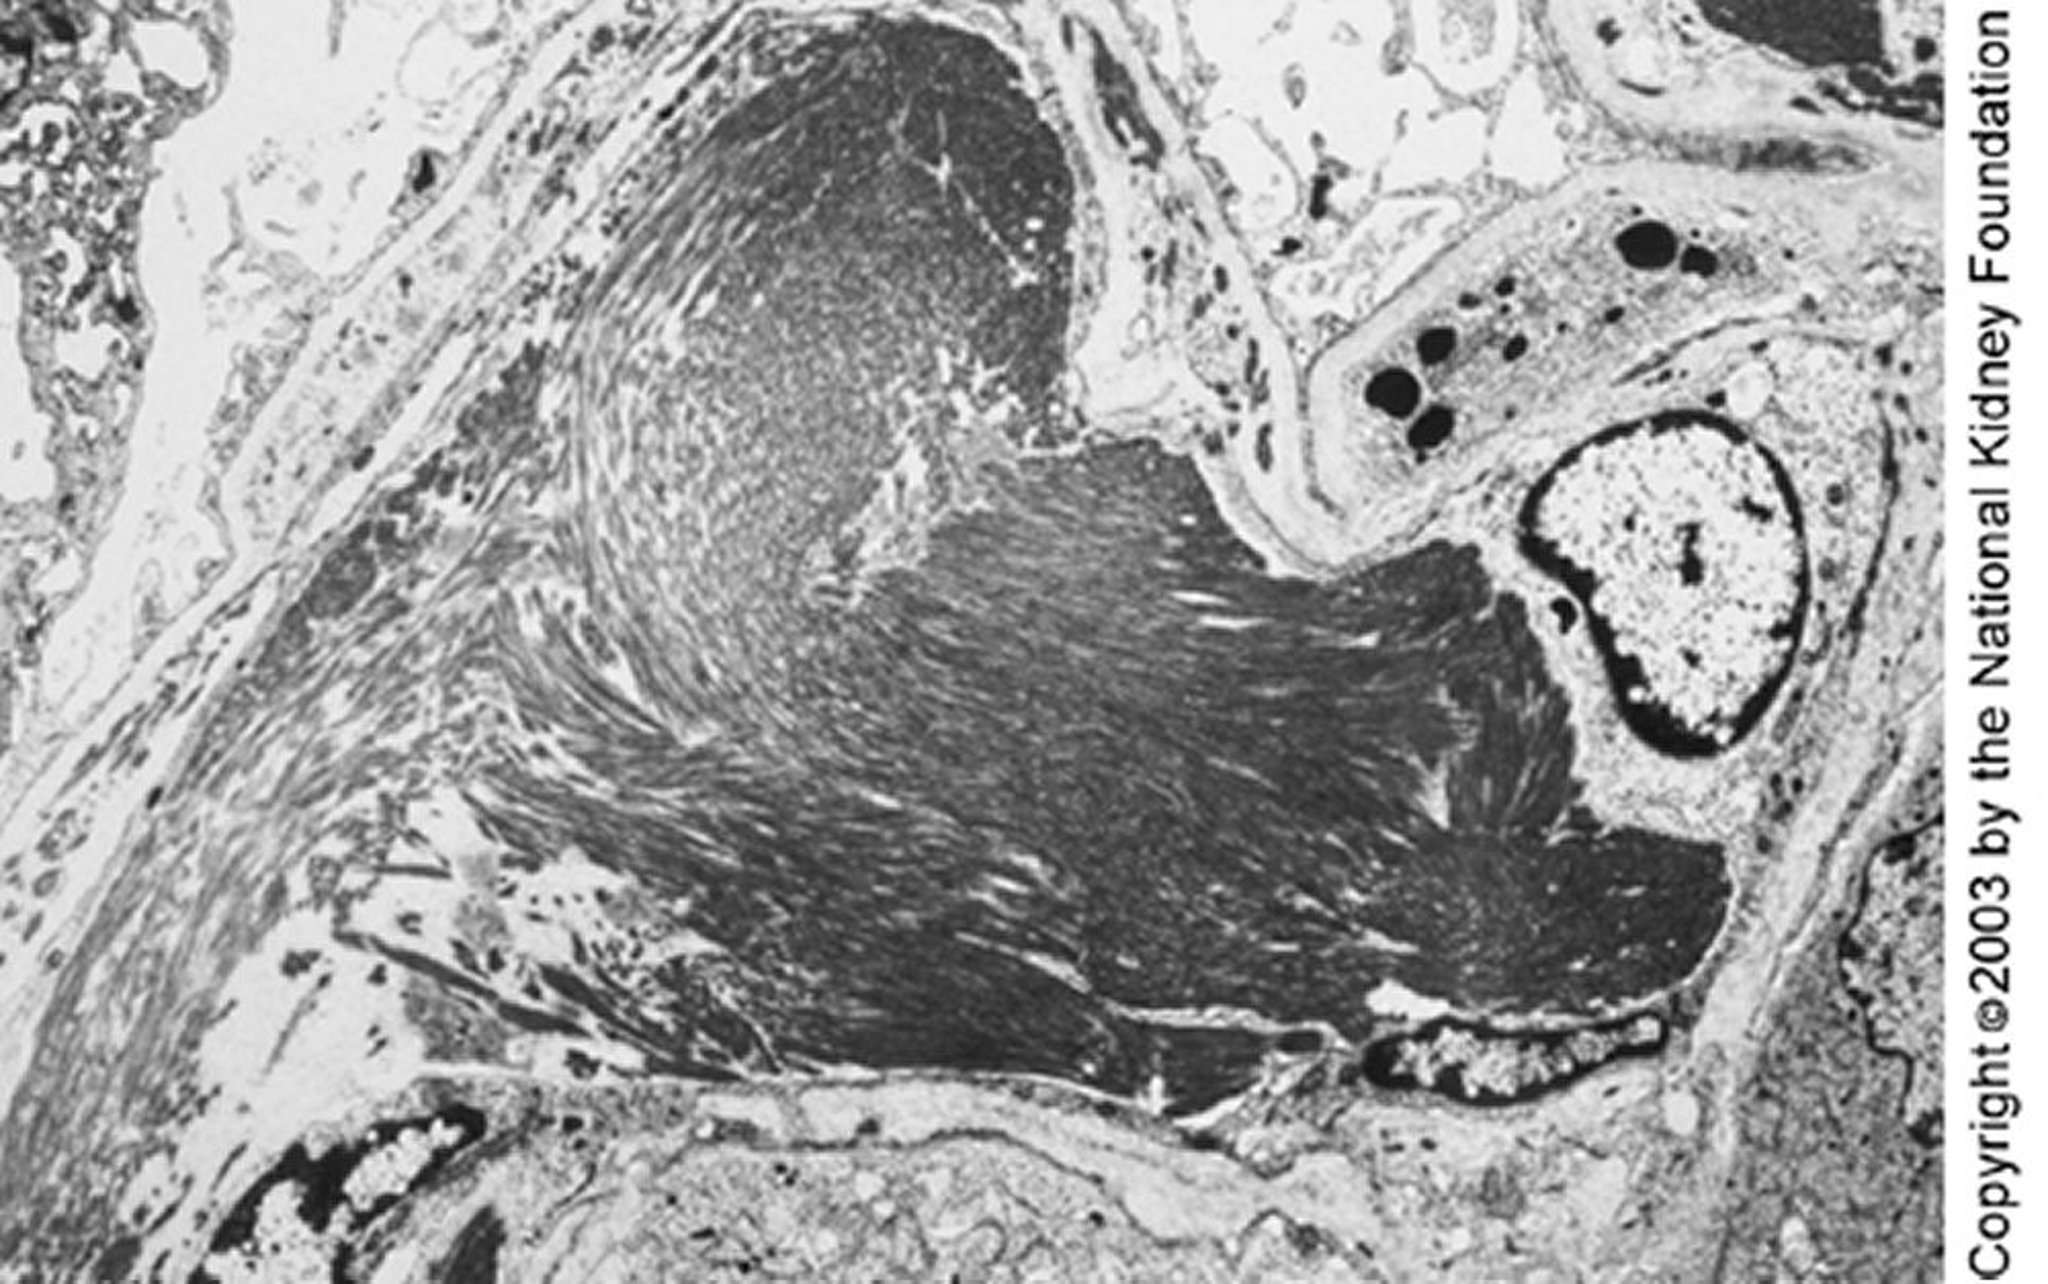

Glomerulopatia imunotactoide

Pode-se observar grandes microtúbulos (diâmetro de quase 50 nm) organizados em arranjos paralelos pela microscopia eletrônica. Os depósitos paralelos e a estrutura microtubular podem diferenciar a glomerulopatia imunotactoide da glomerulopatia fibrilar (×4000).

Image provided by Agnes Fogo, MD, and the American Journal of Kidney Diseases' Atlas of Renal Pathology (see www.ajkd.org).